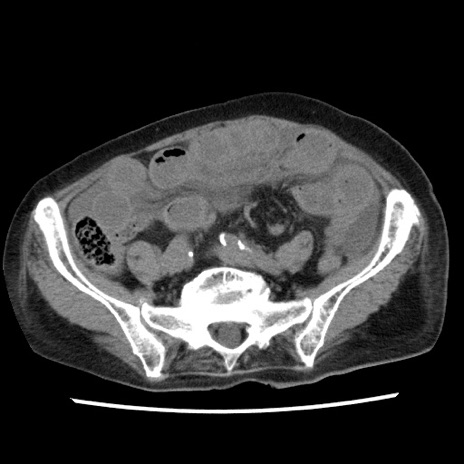

症例1(横断像)

【症例】80歳代女性

【主訴】腹痛

【現病歴】8時間前から腹痛あり来院。

【既往歴】糖尿病、脂質異常症、子宮体癌にて子宮全摘術

【身体所見】意識清明・会話良好だが腹痛で苦悶様、全腹部にわたって反跳痛と圧痛あり

【データ】WBC 13600、CRP 0.14、LDH 224、CK 90